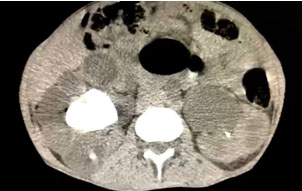

The patient was submitted to an abdominal computed tomography (CT) scan that revealed giant vesical calculus measuring 17.0 × 13.0 × 16.0 cm and volume of 1838 cm3 (Figure 2). Computed tomography also revealed staghorn calculus in the right kidney with 1297 Hounsfield unity (HU) density and intense hydronephrosis and loss of corticomedullary relation and the left kidney with non-obstructive 1.4 cm calculi and moderate hydronephrosis due to vesical obstruction (Figure 3).

Figure 3: Staghorn calculus in the right kidney with renal exclusion and the left hydronephrosis due to bladder obstruction caused by large stone.